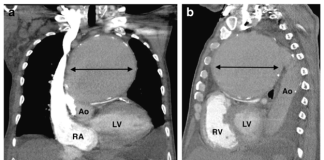

Xử trí dị vật buồng tim: Nhân một trường hợp lâm...

BS.CK2 HUỲNH THANH KIỀU(*)

BS.CK1 PHẠM PHONG LUÂN(*)

PGS.TS. BS PHẠM NGUYỄN VINH(*)

THS. BS. TRẦN THÚC KHANG(*)

BS. NGUYỄN THỊ NGỌC HÂN(**)

(*) Trung tâm Tim mạch, BV Tâm Anh TP. HCM

(**) TT Chẩn đoán hình ảnh, BV Tâm Anh TP. HCM